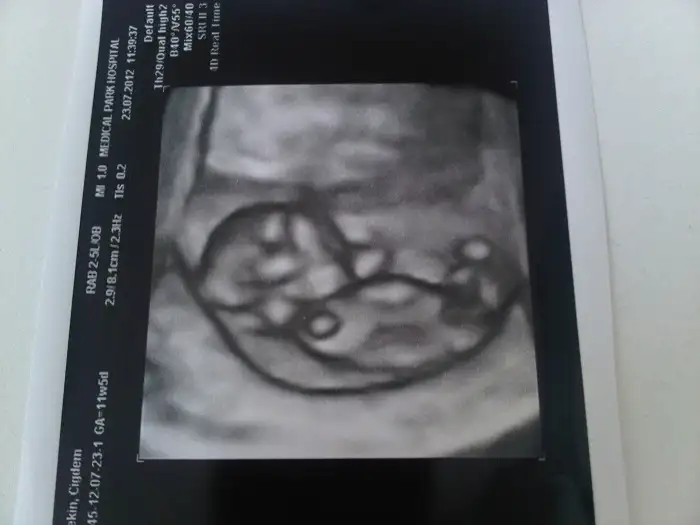

Ultrason resmi şöyle ;

Eki Görüntüle 473354

belfü, ultrason resmine bayıldım. küçük bi bebek var orda, ilk aylardan ne kadar farklı ya. Resmen büyüyolar her geçen gün,Allahın mucizesi işte. Benim bebişin son durumu nasıl acaba:)